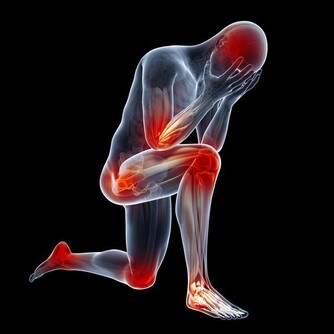

要想知道吃酸味食物會不會影響骨骼發育,建議大家先來看看骨頭的構成。

骨質的成分主要有兩類,一類是有機成分,另一類是無機成分。

有機成分一般是指骨頭里面的細胞、膠原蛋白質、纖維及血管組織等,這些成分賦予骨的彈性和韌性;

無機成分是指構成骨的一些礦物質,主要是使骨骼堅硬結實的鹼性磷酸鈣鹽。

正常情況下,骨的有機成分和無機成分各佔一定的比例。適當的比例能使骨頭既堅硬又柔韌,既不會出現“軟骨頭”的情況,也不會出現骨頭像玻璃那樣很硬,但同時也很脆弱,一碰就碎的情況。

骨質的這兩種成分均受機體內的生物和化學環境影響。其中,鹼性磷酸鈣鹽等無機成分主要受人體內的液體環境影響,體液的酸鹼性對其影響尤其大。

雖說在偏酸的環境下,鹼性磷酸鈣鹽容易溶解,導致骨骼內的有機成分相對較多,並因此使骨骼變得韌性有餘,硬度不足。